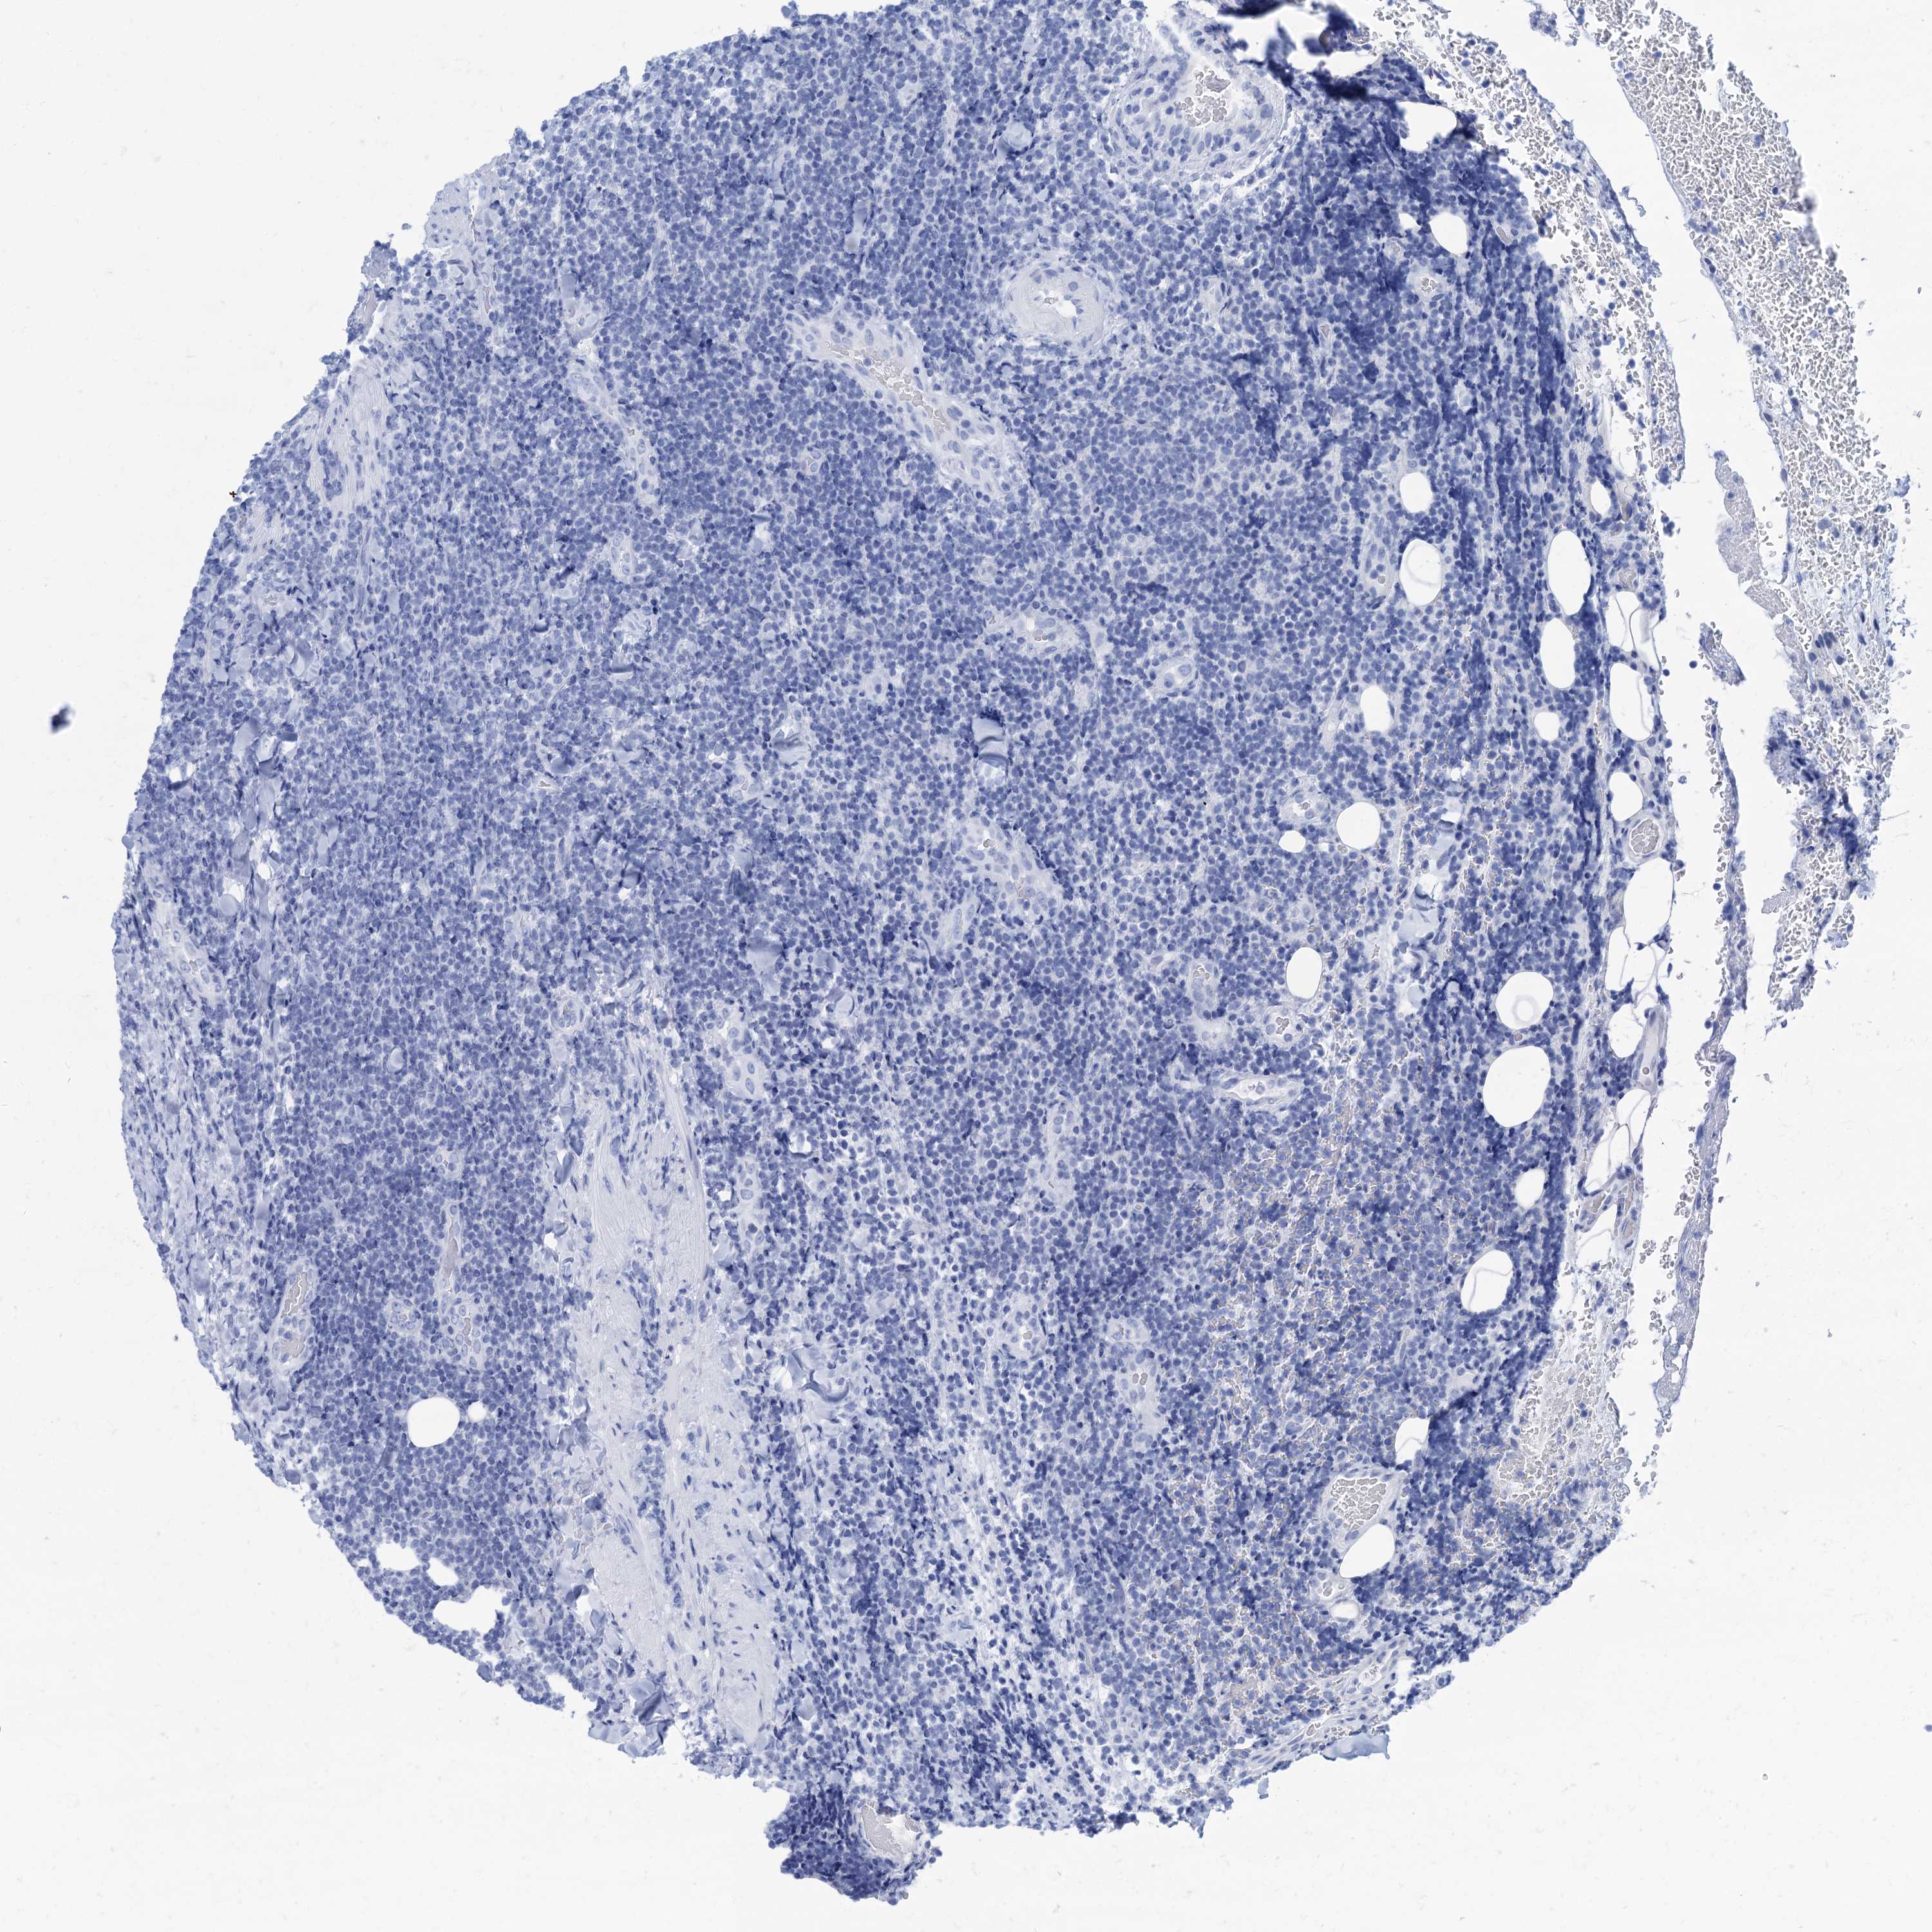

CANCER LYMPHOMA Show tissue menu

LYMPHOMA - Protein expressioni

A mouse-over function shows sample information and annotation data. Click on an image to view it in a full screen mode. Samples can be filtered based on level of antibody staining by selecting one or several of the following categories: high, medium, low and not detected. The assay and annotation is described here.

Antibody staining in the annotated cell types in the current human tissue is reported as not detected, low, medium, or high, based on conventional immunohistochemistry profiling in selected tissues. This score is based on the combination of the staining intensity and fraction of stained cells.

Each image is clickable and will lead to virtual microscopy that enables deeper exploration of all samples and also displays staining intensity scores, fraction scores and subcellular localization as well as patient and tissue information for each sample.

Antibody HPA040703

Antibody HPA047801

Hodgkin's disease, NOS

Malignant lymphoma, non-Hodgkin's type, High grade

Malignant lymphoma, non-Hodgkin's type, Low grade